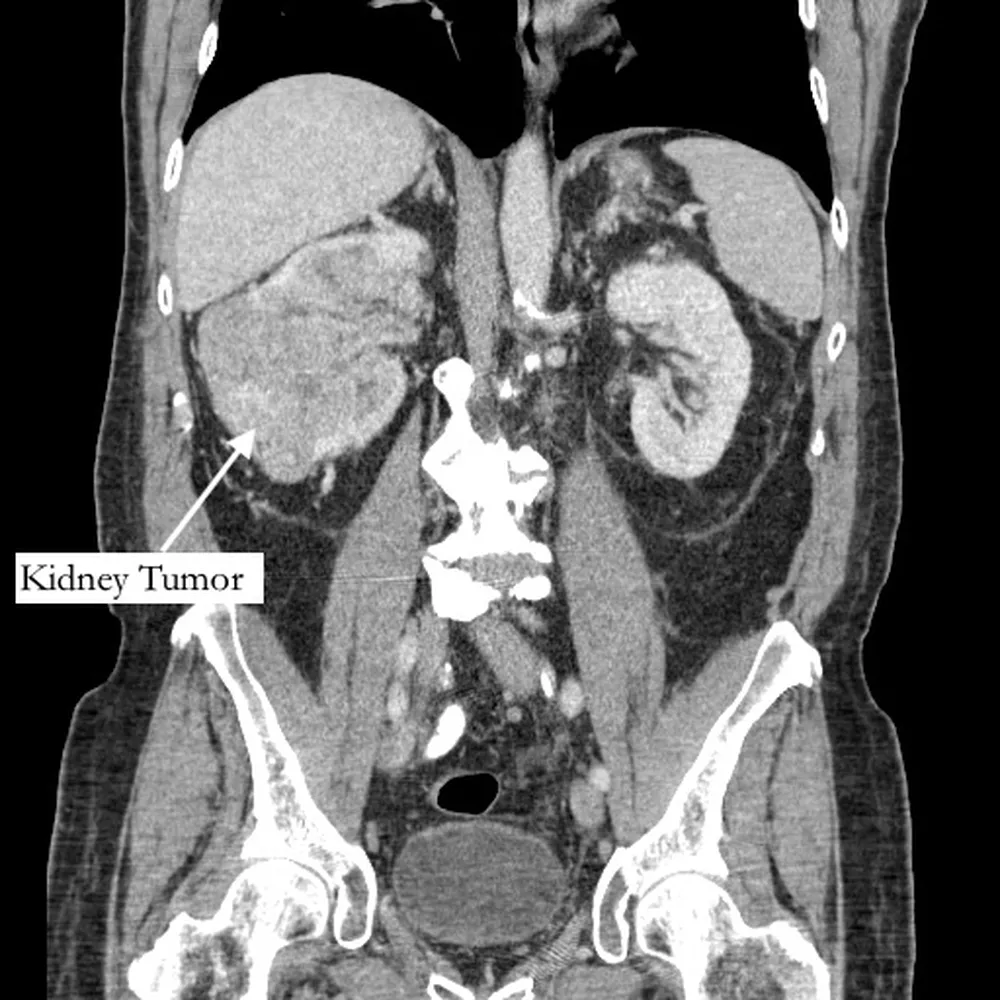

Segundo o jornal “New York Post”, Richard Bernstein, 42, sentia a dor havia cinco anos, e pensava que se tratava de uma fratura, mas recebeu o diagnóstico de grande tumor no rim e de um trombo tumoral, um tumor que se estende até um vaso sanguíneo.

O exame, encaminhado a um urologista, identificou ainda um trombo (coágulo no sangue) que cresceu através da veia renal e preenchia a veia cava, que drena sangue para o coração, e tinha 99% das artérias da coronária bloqueadas, além do fígado quase entrando em falência.

Segundo o diretor de urologia do Hospital Phelps, no estado de Nova York, Michael Grosso, o bloqueio de veias por conta do tumor e do trombo era o que explicava a dor no pé do aposentado, já que os sintomas de câncer no fígado costumam surgir já em uma fase avançada do tumor.

O paciente passou então por uma cirurgia de urgência para remover o tumor.

Após 12 horas de uma cirurgia complexa e casada entre médicos de diferentes especialidades, o tumor e o trombo foram retirados e uma ponte de safena foi realizada.